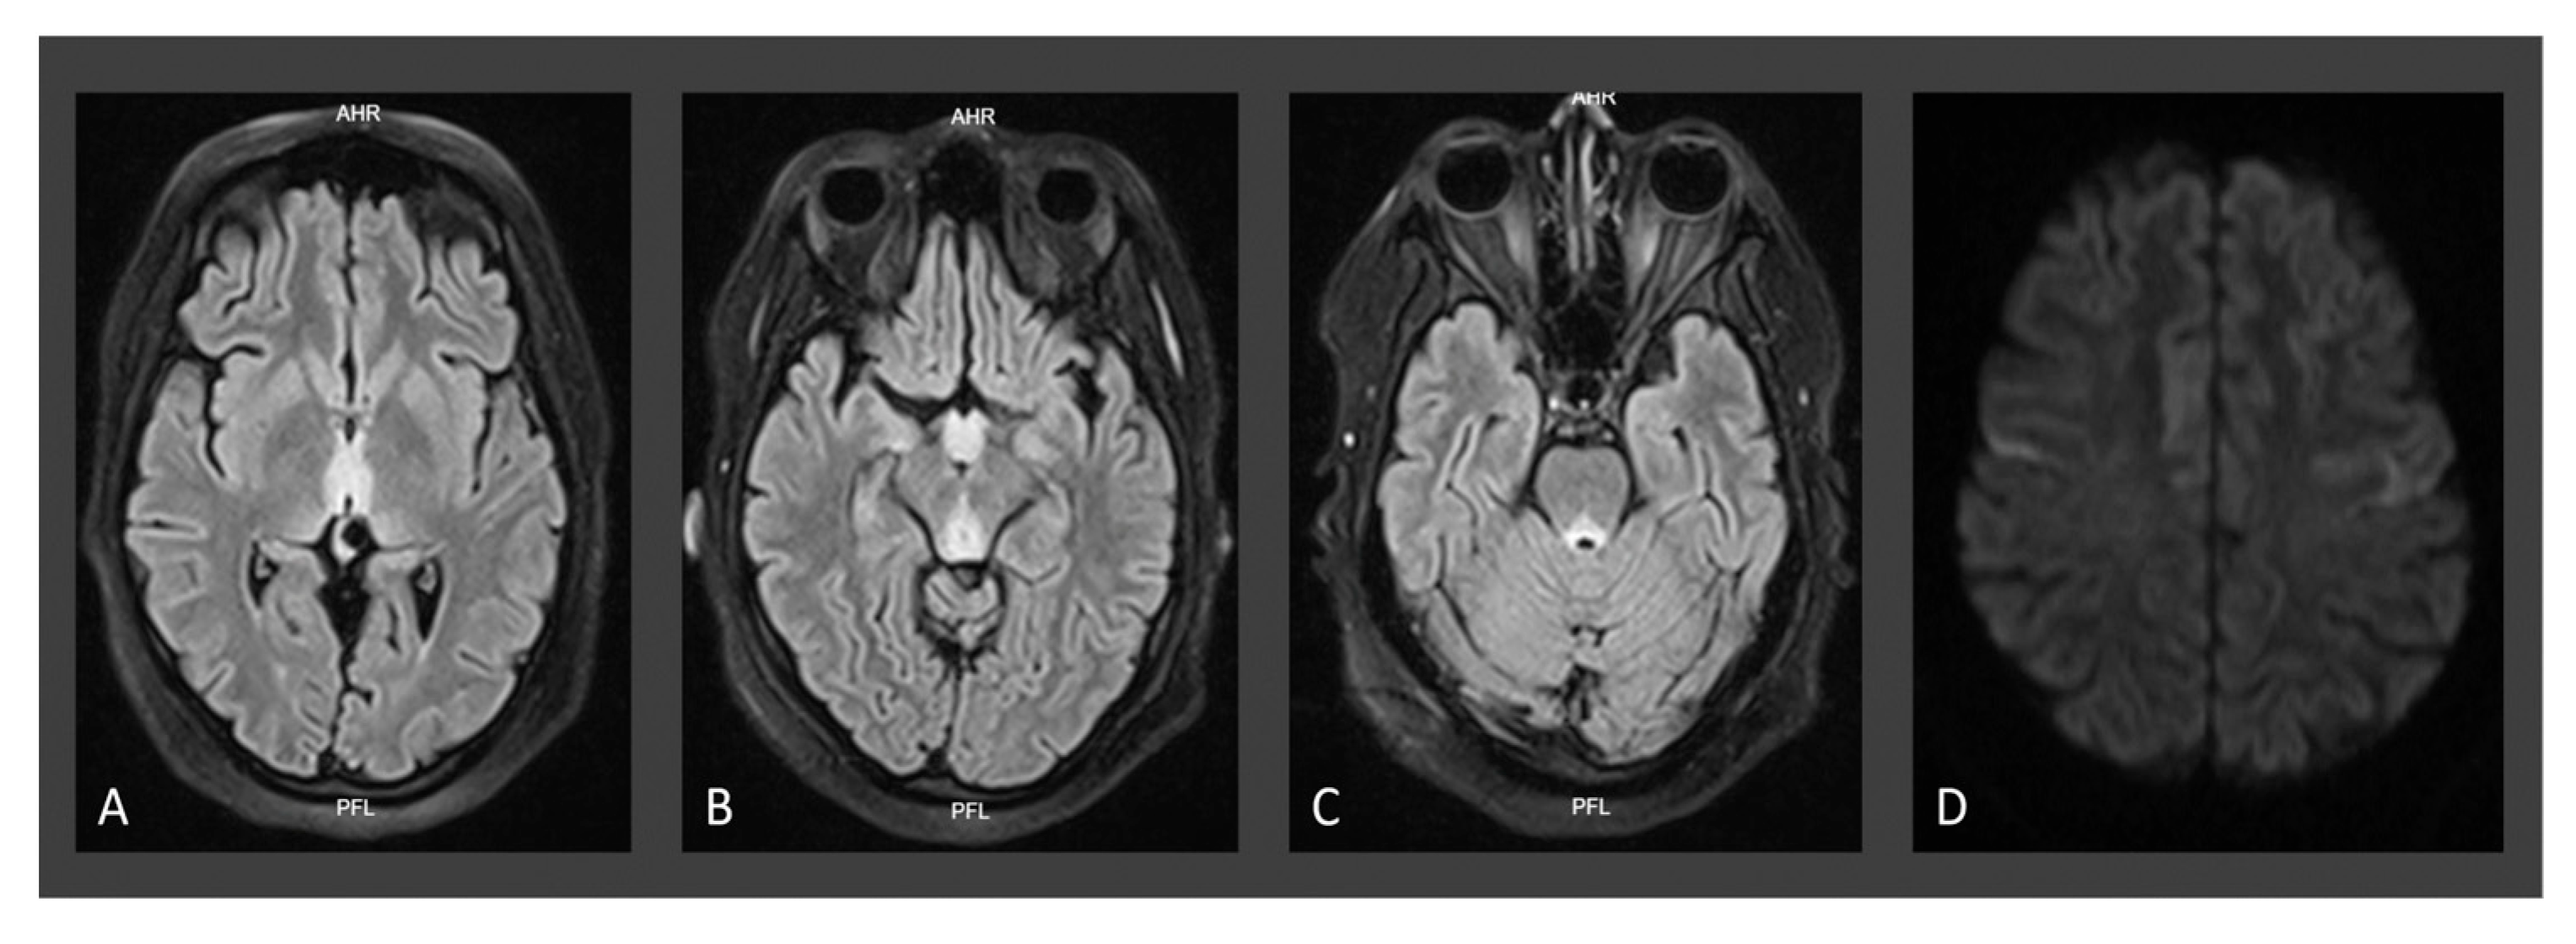

| Neuroimaging for W.D. | Typical | Typical | Typical |